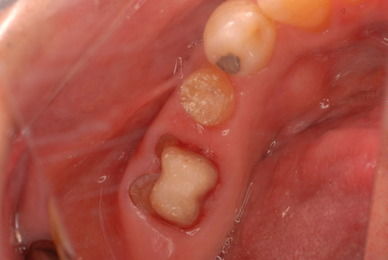

左下の歯は歯の中の治療も?ですごい歯周病を患い歯茎の穴(ポケットと呼ばれるところ)から膿が出ているのです。ばい菌と毒素で骨が溶けて深い穴ができてそこにまたバイキンと毒素がたまるという悪循環ができているのですね。

右下の歯は歯の中の治療もあやしいのですが、金属と歯の間がすでに虫歯で崩壊し始めています。

プラークというバイキンと毒素と食べかすの塊が歯の周りや歯茎にまとわりついて虫歯になり且つ重症の歯周病を患っています。